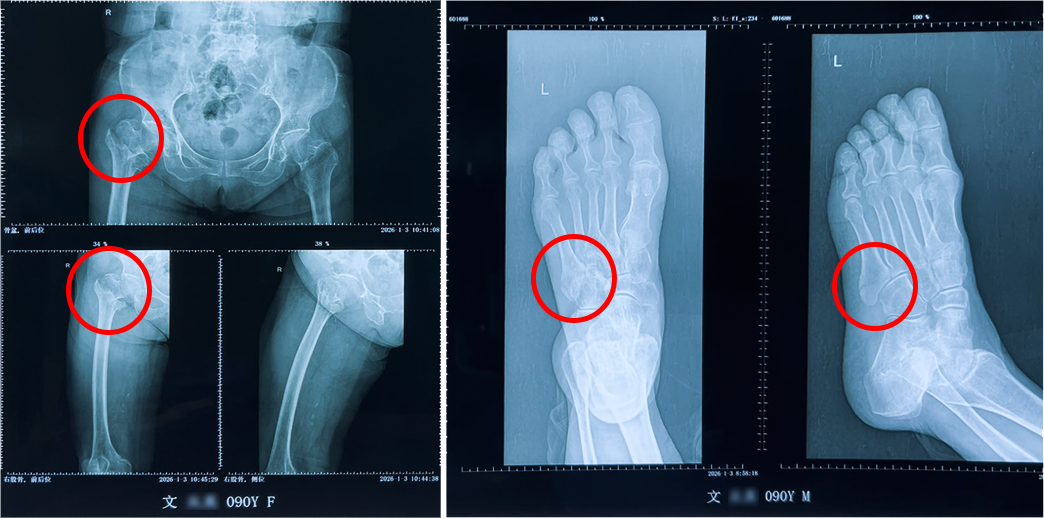

本年1月初,乐鱼体育文奶奶在家中失慎跌倒,导致右股骨粗隆间骨折并伴有左足第五跖骨骨折,被稠密送入深圳永福病院。